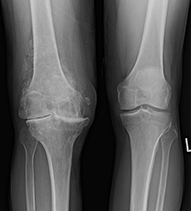

OSTEOARTHRITIS OF THE KNEE

Osteoarthritis (‘wear and tear’) of the knee is a common condition. It can affect the entire joint or just one compartment of the knee joint. Patients often experience pain which is related to activity, and find that rest relieves the pain.

This is a slowly deteriorating condition, and there comes a time when some patients find that the knee is sore for the majority of the time when they are walking. In such cases, if all non-surgical methods of treatment have been exhausted, including physiotherapy, weight loss and pain-killers, partial or total knee replacement will be considered.